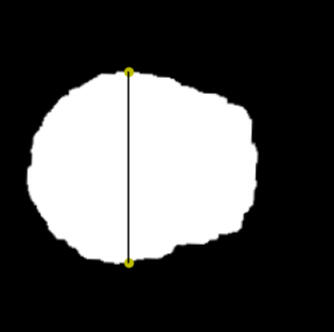

Automatic measurement of Callosal angle (CA), Evans index (EI), 3D EI and cDESH